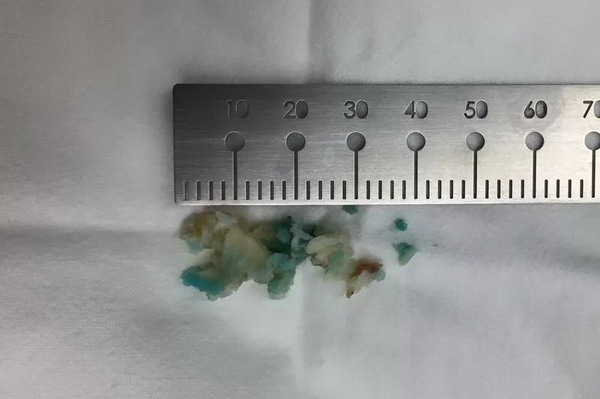

▲摘除已突出的椎间盘组织(染色 )

▲手术伤口仅1厘米

整个手术没有传统手术的紧张氛围,仅在局麻下进行,患者全程保持清醒。手术中,赵叔右大腿的痹痛即刻缓解,右侧股神经牵拉试验(-)阴性,恢复正常!手术伤口仅有“1厘米”,术后第一天,赵叔已经可以佩戴腰围下地活动了,之前站立及行走的疼痛症状也随微创手术消失。

不可思议的是,术后第二天,赵叔就在医生的安排下开开心心地出院回家了。